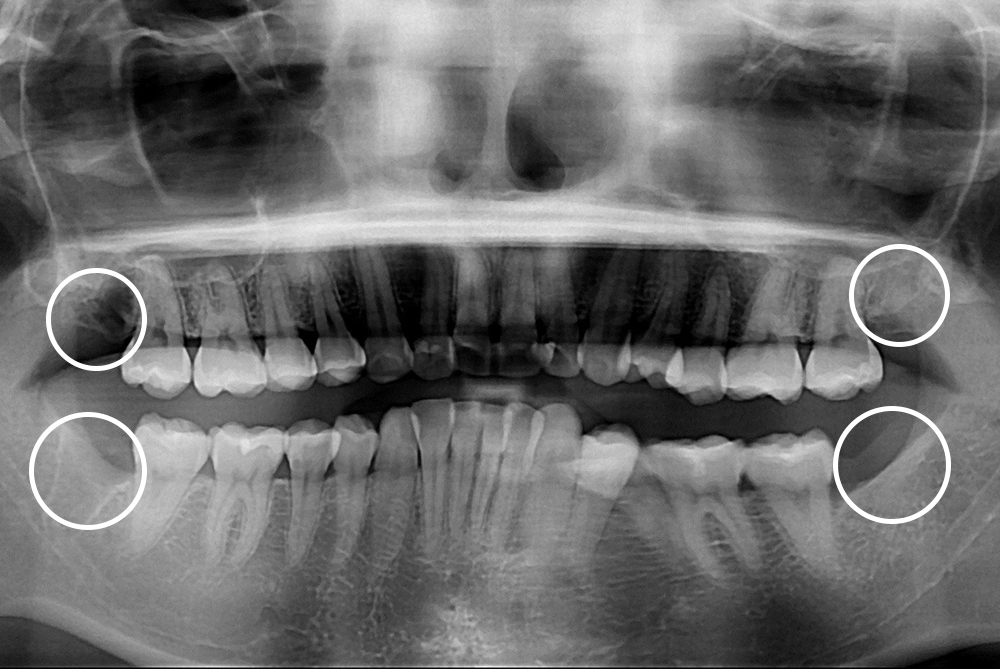

[사랑니] 매복 사랑니 발치

치료후 : 2019-06-28

세종치과는 구강악안면외과학 박사이신 원장님이 발치하는 치과입니다.